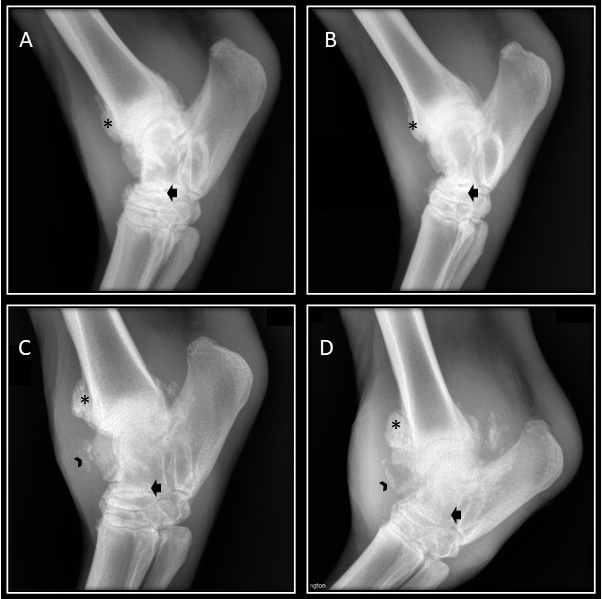

Según lo encontrado al examen clínico y la ecografía se decide realizar un estudio radiológico ortogonal de tarso y de menudillo (desplazamiento de la articulación interfalángica proximal en el examen clínico) del miembro posterior derecho, dicho estudio se realizó varias veces a lo largo de la evolución del caso clínico, siendo que se tomaron vistas radiográficas en el momento inicial del caso, a los 15 días posteriores, a los 4 meses después y un año después (Figura 2). En el examen inicial se realiza una vista lateral del tarso se observa un área de proliferación y reacción perióstica moderada en el aspecto dorsal de la porción distal de la tibia, así mismo en la porción dorsal del tarso central y del tercer hueso tarsiano, la fosa lateral del talus presenta un aspecto radiopaco poco definido, no es posible observar el espacio de la articulación talo-calcanea lateral, evidencia los tubérculos del calcáneo de aspecto poroso, se observa aumento del tamaño del tejido blando en el aspecto dorsal de la articulación (Figura 3).

Radiografía lateral de tarso en la cual se observa reacción proliferativa en la región distal de la tibia (*), se observa un proceso de lisis ósea generalizada en el aspecto dorsal del astrágalo (punta de flecha), a su vez, se evidencia pérdida de los espacios articulares (flecha), reacción osteofítica marcada y aumento de la densidad del tejido blando periarticular. La radiografía A, corresponde al momento inicial del caso, la radiografía B, se realizó 15 días después, radiografía C, se realizaron 4 meses después, radiografía D, un año después.

En el abordaje anteroposterior se encuentra proliferación ósea y reacción perióstica del maléolo medial de la tibia el cual presenta una superficie irregular y disminución de la densidad, lo cual, se hace generalizado para el aspecto medial y lateral del astrágalo, se observa disminución del espacio articular entre las articulaciones intertarsianas proximales e intertarsianas distales, hay lisis óseas en el cuarto hueso tarsiano, finalmente se hace evidente el aumento de tamaño del tejido blando en los aspectos mediales y laterales de la articulación tarsiana . En la radiografía lateral del menudillo se encuentra luxación de la articulación interfalángica proximal, los sesamoideos proximales se observa con un patrón apolillado con múltiples zonas focales de lisis ósea y perdida de densidad. Con la evolución del proceso inflamatorio articular se evidenciaron severos cambios relacionados con lisis ósea, aumento de la reacción proliferativa, y deformación severa de la articulación tarso-tibial, estos procesos fueron observados a los 4 meses y al año posterior al inicio del caso clínico.

Hardy (11), menciona que el estudio radiográfico en pacientes con enfermedad articular es necesario ya que puede correlacionarse con los hallazgos clínicos presentes en el examen físico del paciente, a su vez describe lesiones como disminución de la opacidad a nivel del hueso cortical, reacción perióstica exacerbada, aumento del tamaño y la densidad de la cápsula articular y aumento del líquido sinovial (11), en un estudio realizado por Raes (12), encontró que el 69.7% (62/89) de los animales evaluados tuvieron hallazgos radiográficos relacionados con lesiones compatibles con artritis (12), estos hallazgos radiológicos se relacionan con el estudio realizado ya que la paciente presentó aumento del tamaño articular, área de proliferación y reacción perióstica moderada en el aspecto dorsal de la porción distal de la tibia, porción dorsal del tarso central y del tercer hueso tarsiano; la fosa lateral del talus presenta un aspecto radiopaco poco definido, no es posible observar el espacio de la articulación talo-calcánea lateral, se evidencia los tubérculos del calcáneo de aspecto poroso, se observa aumento del tamaño del tejido blando en el aspecto dorsal de la articulación.